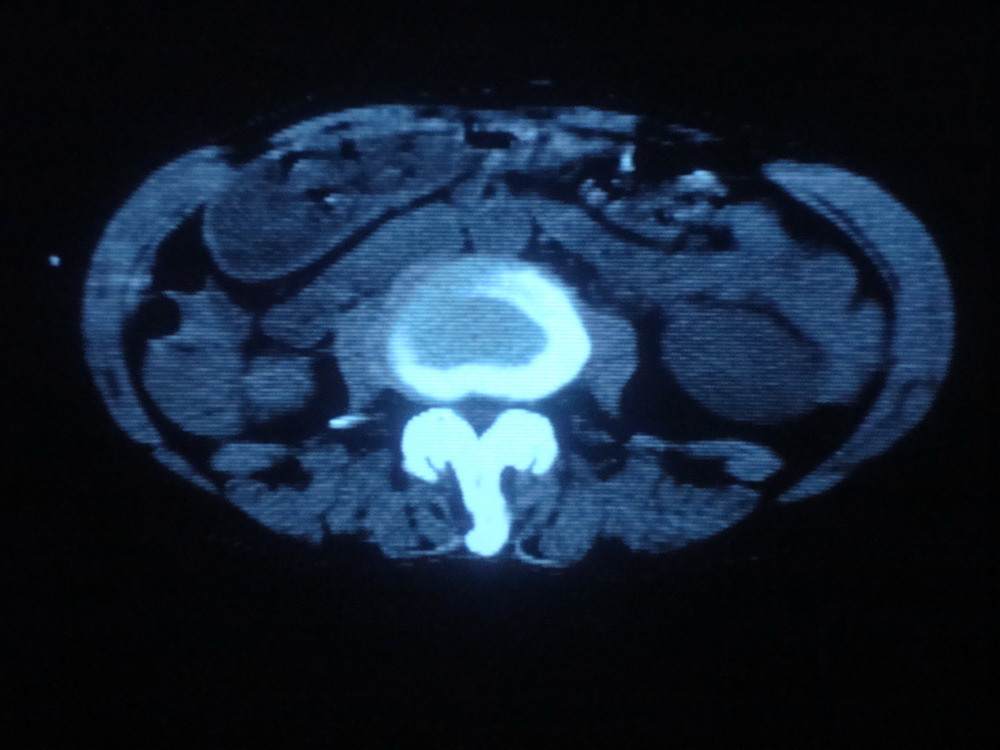

以下是引用卜一在2009-4-1 19:39:00的发言:[br]右肾发育不全、结石、积水并感染可能;左肾结石,代偿性增大。支持!

以下是引用随缘的人在2009-4-1 20:42:00的发言:[br]右肾发育不全、结石、积水并感染可能;左肾结石,代偿性增大。支持!